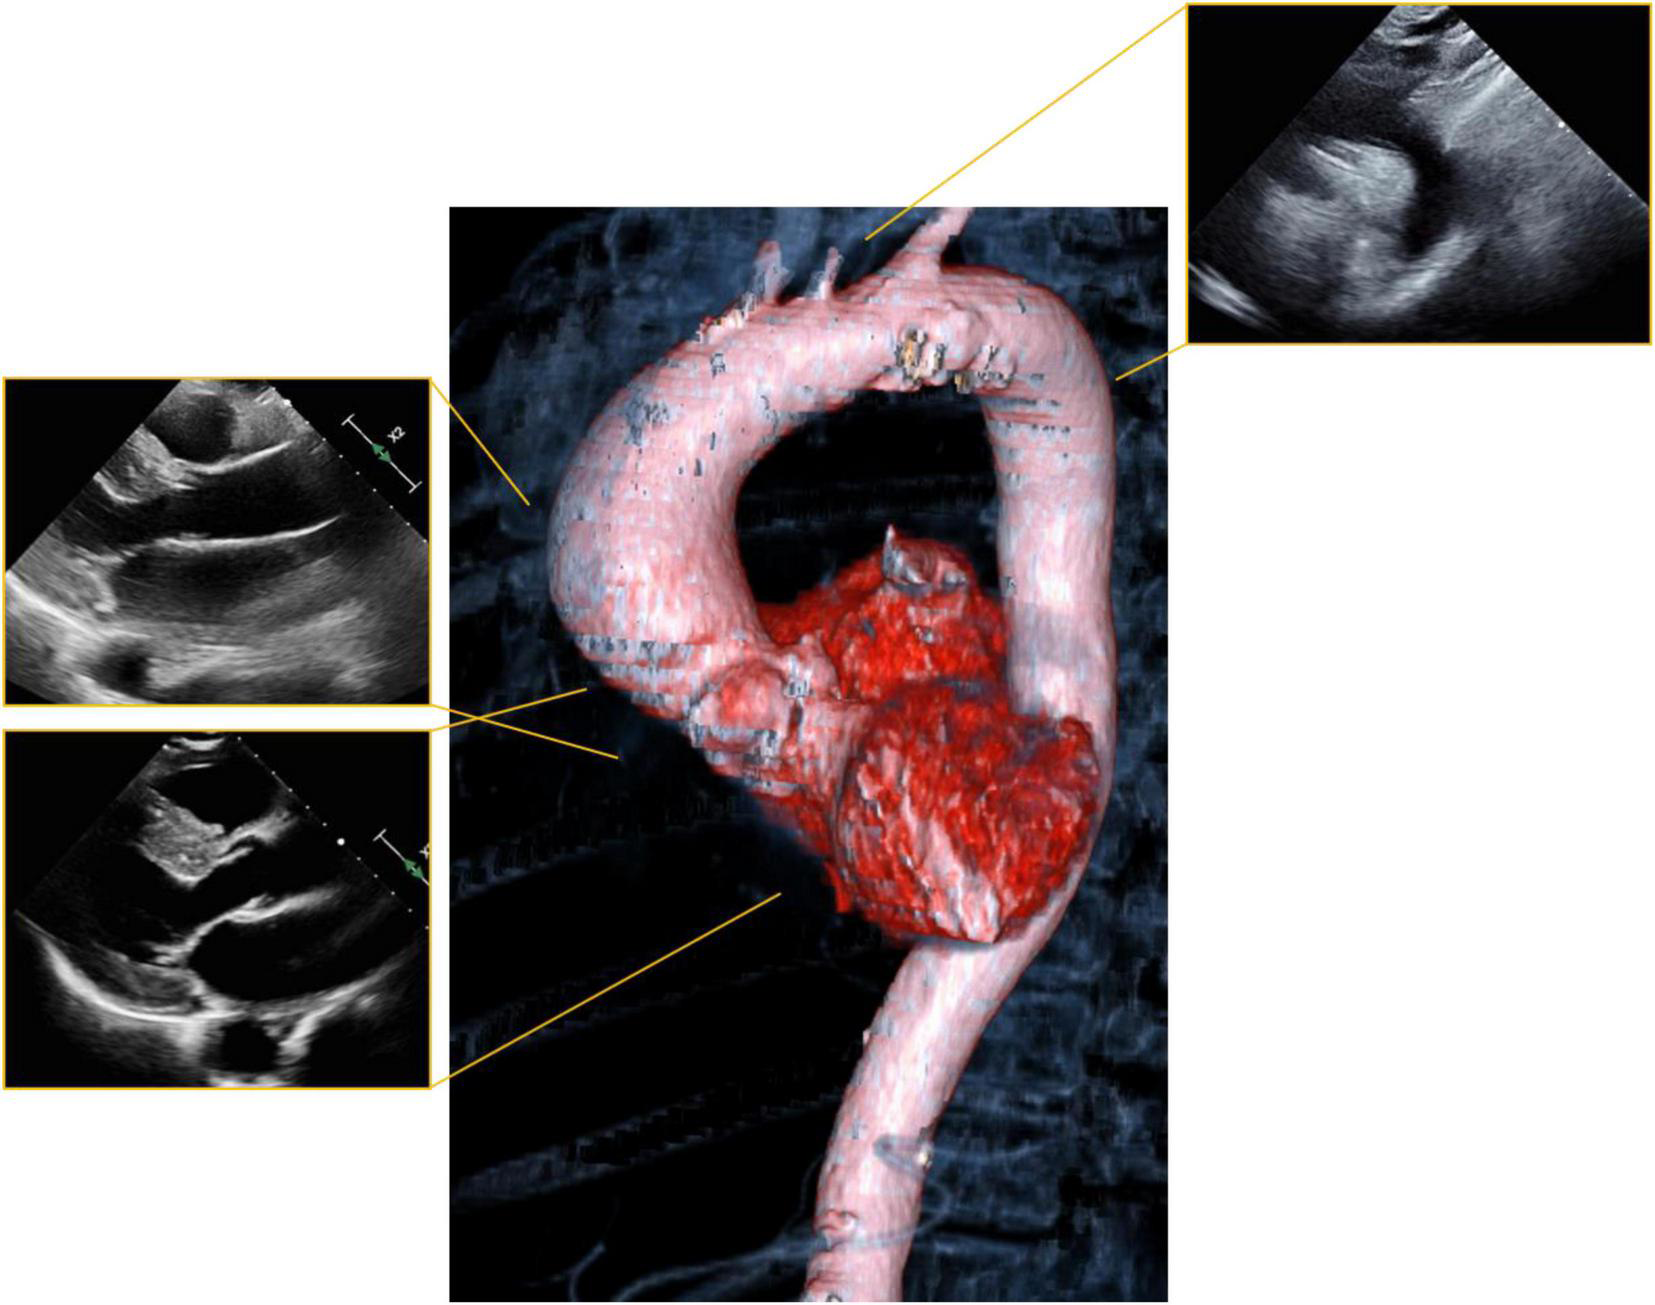

The choice of imaging modality is therefore based on the reliability and accuracy of the modality for evaluation of the pathology in question, as well as safety for the mother and fetus. Echocardiography has essentially no safety concerns for the mother or fetus during pregnancy and remains the fundamental imaging modality for assessment of myocardial and valvular disease. However, imaging may be limited due to patient positioning and the gravid uterus (4). In particular, echocardiographic visualization of the aorta is often limited to the aortic root and proximal ascending aorta (Figure 1). Although echocardiography offers the greatest safety from a procedural standpoint, this must be weighed against the risk of missed or inadequately-characterized aortic pathology. We briefly review the existing data regarding use of CT and MRI in pregnancy.

FIGURE 1

Visualization of the aorta with echocardiography. Standard parasternal and suprasternal notch views (periphery) leave a significant portion of the aorta unvisualized. Computer tomography (CT) or magnetic resonance imaging (MRI) can visualize the aorta in three dimensions (center) and allows for comprehensive evaluation of anatomy.

Aortopathy

Pregnant women with aortopathy should undergo serial echocardiography. Echocardiography should be performed monthly in women with significant aortic dilatation (4–4.5 cm for Marfan’s syndrome, 4.5–5.0 cm for bicuspid aortic valve), but is reasonable to be performed every 12 weeks in women with mild aortic dilation. If necessary, because of poor visualization by echocardiography (Figure 1), location of the aortic dilation, or suspected progression, cardiac MRI without contrast can be used for further assessment and follow up (21, 64).